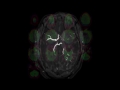

Moyamoya Secondary to Sickle Cell Disease

In this 36-year-old female with a history of sickle cell disease, the first image, an ADC map, demonstrates focal regions of diffusion restriction compatible with acute infarcts in the subcortical and deep white matter of the left frontal and parietal regions. The arterial spin label perfusion images, images 2 and 3, demonstrate regions of decreased perfusion, discrepent with the corresponding ADC map representing the presence of an ischemic penumbra, in the right frontal region, left frontoparietal region, and and left cerebellar hemisphere. On the postcontrast axial T1-weighted sequence centered at the level of the Circle of Willis, image 4, a normal appearing left internal carotid terminus is not visualized. Instead, a tangle of vessels is identified extending along the first segments of the anterior and middle cerebral arteries on the left. These findings are confirmed on the coronal postcontrast T1-weighted sequence, image 5. This patient had a prior history of multifocal cerebral infarctions in the setting of sickle cell disease. These images confirm a disgnosis of Moyamoya disease along the left anterior and middle cerebral artery territories. These findings are confirmed on the MR angiography MIP reconstruction, image 6. Moyamoya disease is a result of progressive stenosis and then occlusion of the distal internal carotid arteries and their proximal first-order branches. Extensive collaterals develop at the level of the stenosis and occlusion and may result from dural vessels, leptomeningeal collaterals, and deep perforating lenticulostriate arteries, as in this case. Moyamoya is classically described as a hazy-like puff of smoke on diagnostic angiography.